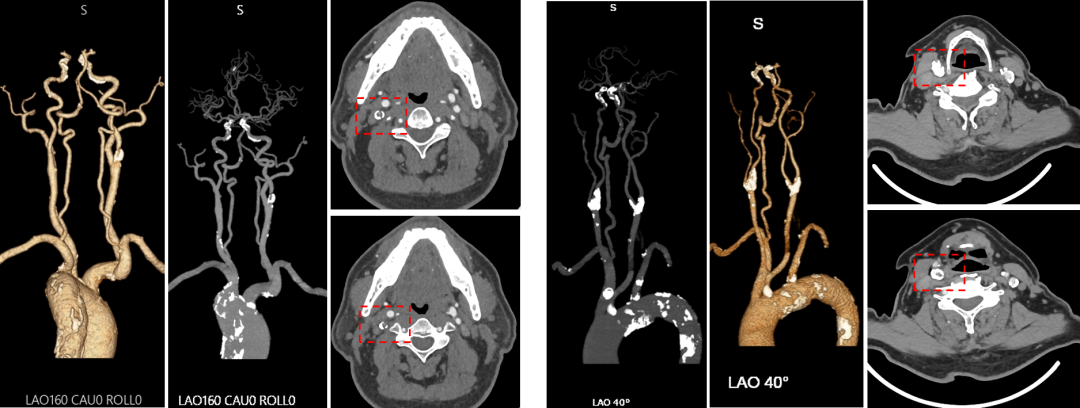

支架选择:目前国内获批的颈动脉球囊、支架均可适配TCAR装置。本组中使用最多的为Precise(开环支架,占比56%),但临床实践中,应根据病变形态(钙化、迂曲、分叉角度)灵活选择开环或闭环支架。

双支架置入:本组中有10例患者置入两枚支架。其中2例明确因斑块脱垂导致。这提示对于斑块负荷极重、质地松软的患者,即使有逆向血流保护,支架释放后仍需警惕斑块通过网眼突出。

★ 分叉型病变

颈总动脉分叉位置过高或角度刁钻,不仅通过困难,且支架释放后易挤压、闭塞颈外动脉。